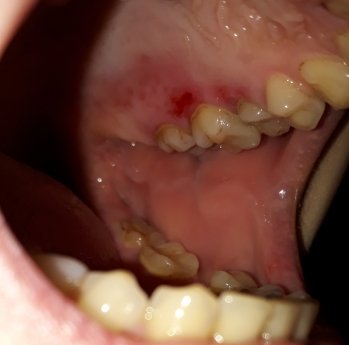

У меня болезнь эпилепсии и гепатит С. У меня кровоточивость десен и ничего не помогает. Я пользуюсь зубной пастой paradontax, применяю для полоскания ополаскиватели и стоматофит. Врач выписывал мне уколы, медикаменты (не помню название), но ничего не помогает. Сейчас болят и кровоточат десна.

Как решить эту проблему?